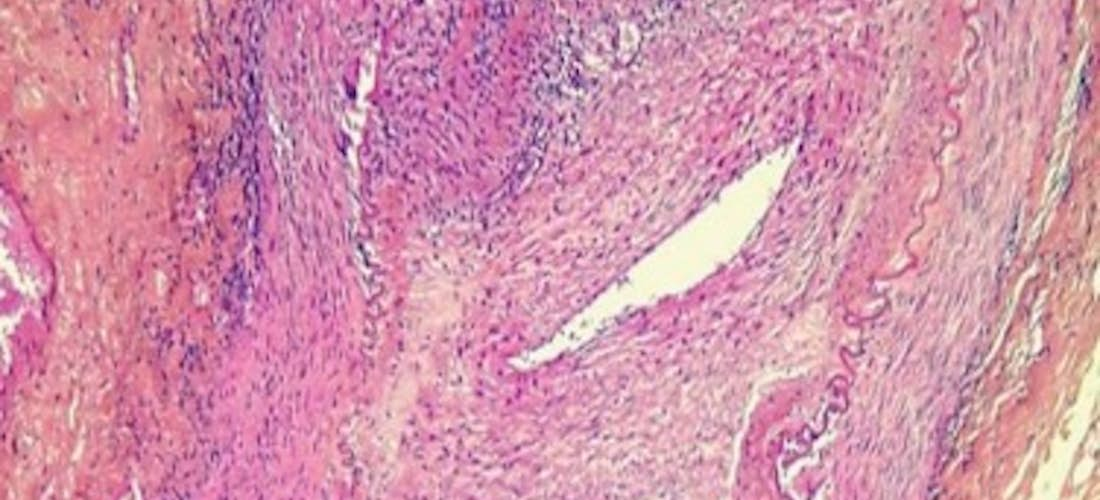

Elle est en fait plus diffuse comme le montrent la clinique et les explorations d‘imagerie. Histologiquement, l'atteinte vasculaire intéresse les trois tuniques, avec un infiltrat inflammatoire essentiellement mononucléé, une destruction du tissu élastique et une réaction histiocytaire à son contact. On observe un épaississement intimal constitué d'une prolifération fibroblastique, et des cellules géantes sont observées au contact de la limitante élastique interne. L'artérite à cellules géantes (maladie de Horton) survient dans la majorité des cas chez les sujets âgés de plus de 50 ans. Sa présentation clinique, très polymorphe, impose de pratiquer, comme pour toute vascularite, une biopsie afin d'en affirmer le diagnostic.